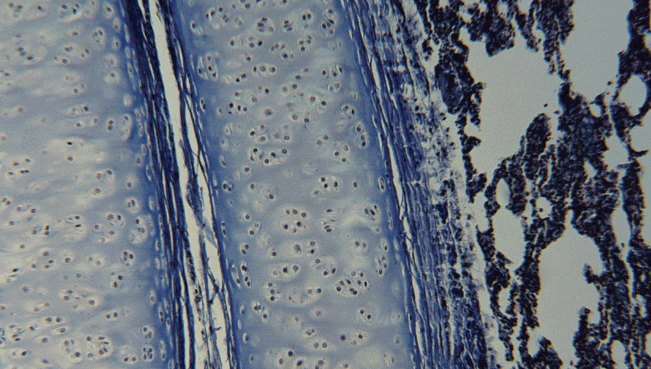

生物顯微成像案例

我們的顯微成像方案,結(jié)構(gòu)和功能各不相同,但核心都是一致的,即模塊化的集成搭建原則、出色穩(wěn)定的光學(xué)成像質(zhì)量。